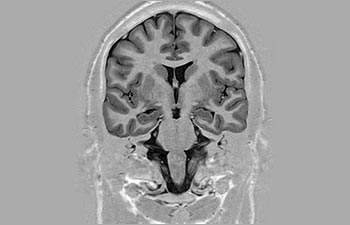

Brain overview